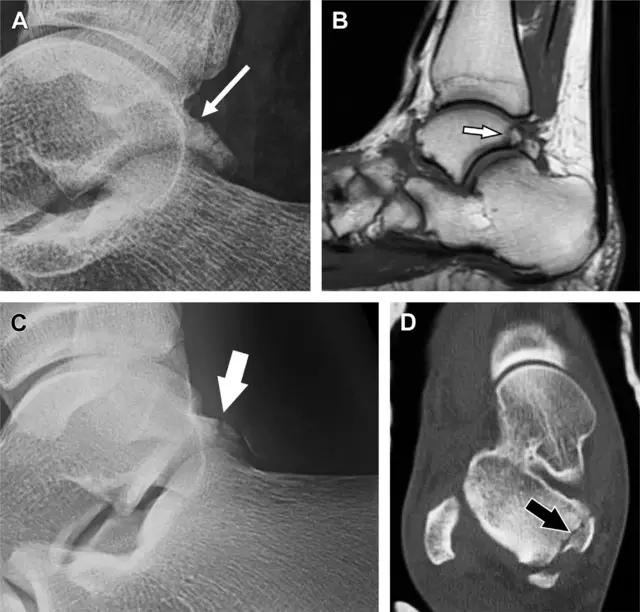

20 跟骨前突骨折

呈 Y 形的分歧韧带附着于跟骨前突上,是维持踝关节跖屈和背屈稳定性的重要结构。跟骨前突骨折常发生于足跖屈内旋、分歧韧带被牵拉时,或者足背屈外旋、骰骨和距骨挤压前突时。而这些骨折在初次 X 线检查时常常被漏诊掉。踝部侧位片诊断这些骨折最佳,准确诊断的关键点在于,必须仔细查看是否存在骨皮质中断(图 6)。如果侧位片可疑,建议加做斜位片协助诊断。

图 6 跟骨前突骨折。A 侧位片示跟骨前突骨折(箭头),与舟骨的重叠使骨折显示模糊;B 另一位患者的侧位片示内翻损伤所致的骨折(箭头),这种损伤机制引起小块的骨折